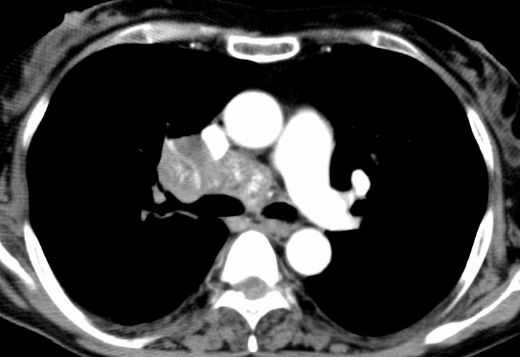

Kalsifikasyonun Tanısı Kalsifikasyonun tanısı, klinik muayene, görüntüleme teknikleri ve laboratuvar testleri ile konulabilir. Yaygın kullanılan yöntemler şunlardır:

Azize Hanım, bu kalfikasyonlar insanlarda ölü dokulardan biriken kireçlenmelerdir. Aşırı bir hale geldiği zaman şişlik şeklinde kendisini gösterebilmektedir. Zamanla kemikleşerek sert bir hale gelebilir. Bu nedenle alınabilecek bir bölgede ise doktorunuzla iletişime geçebilirsiniz.